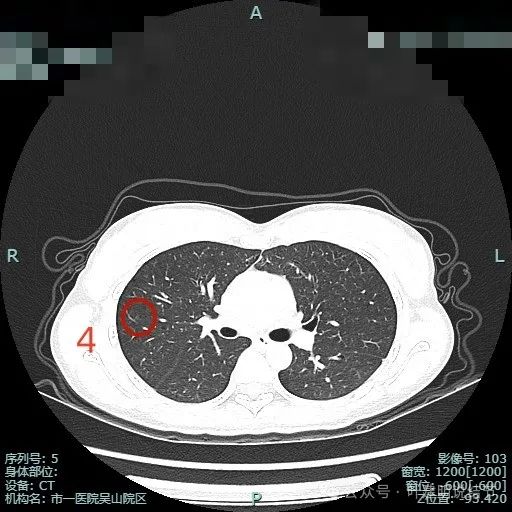

病灶4:右肺微小淡磨玻璃结节,整体轮廓较清,考虑肺泡上皮增生或少放纤维增生可能。